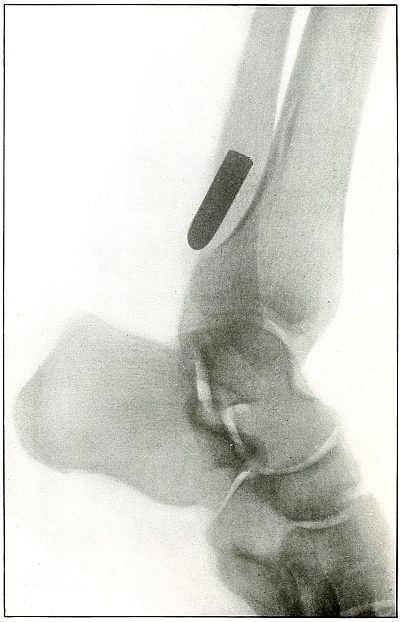

Rifle—Plate 61.

Gunshot Fracture of the Lower Ends of the Tibia and Fibula.

The course of the bullet was transverse, with the velocity of mid-range.

The fragmentation of the fibula, lying close to the skin, would produce considerable laceration in the wound of exit.

The treatment is conservative. Infection would depend almost entirely upon the integrity of the first dressings and immobilization.

Results should be favorable, with care in subsequent treatment. [Pg 134]